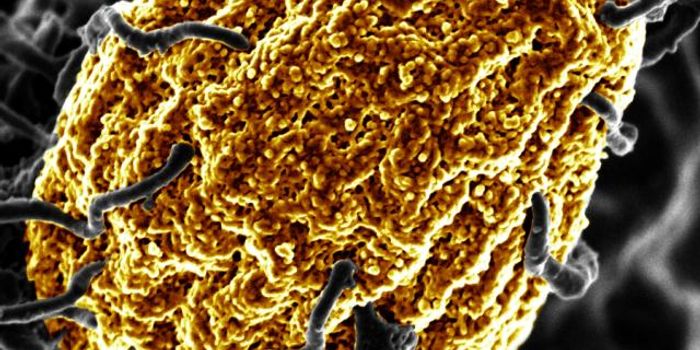

SEP 05, 2024Cell & Molecular BiologyCorynebacterium matruchotii ia a common bacterium that lives in human dental plaque; a colony is seen in this image by S ...